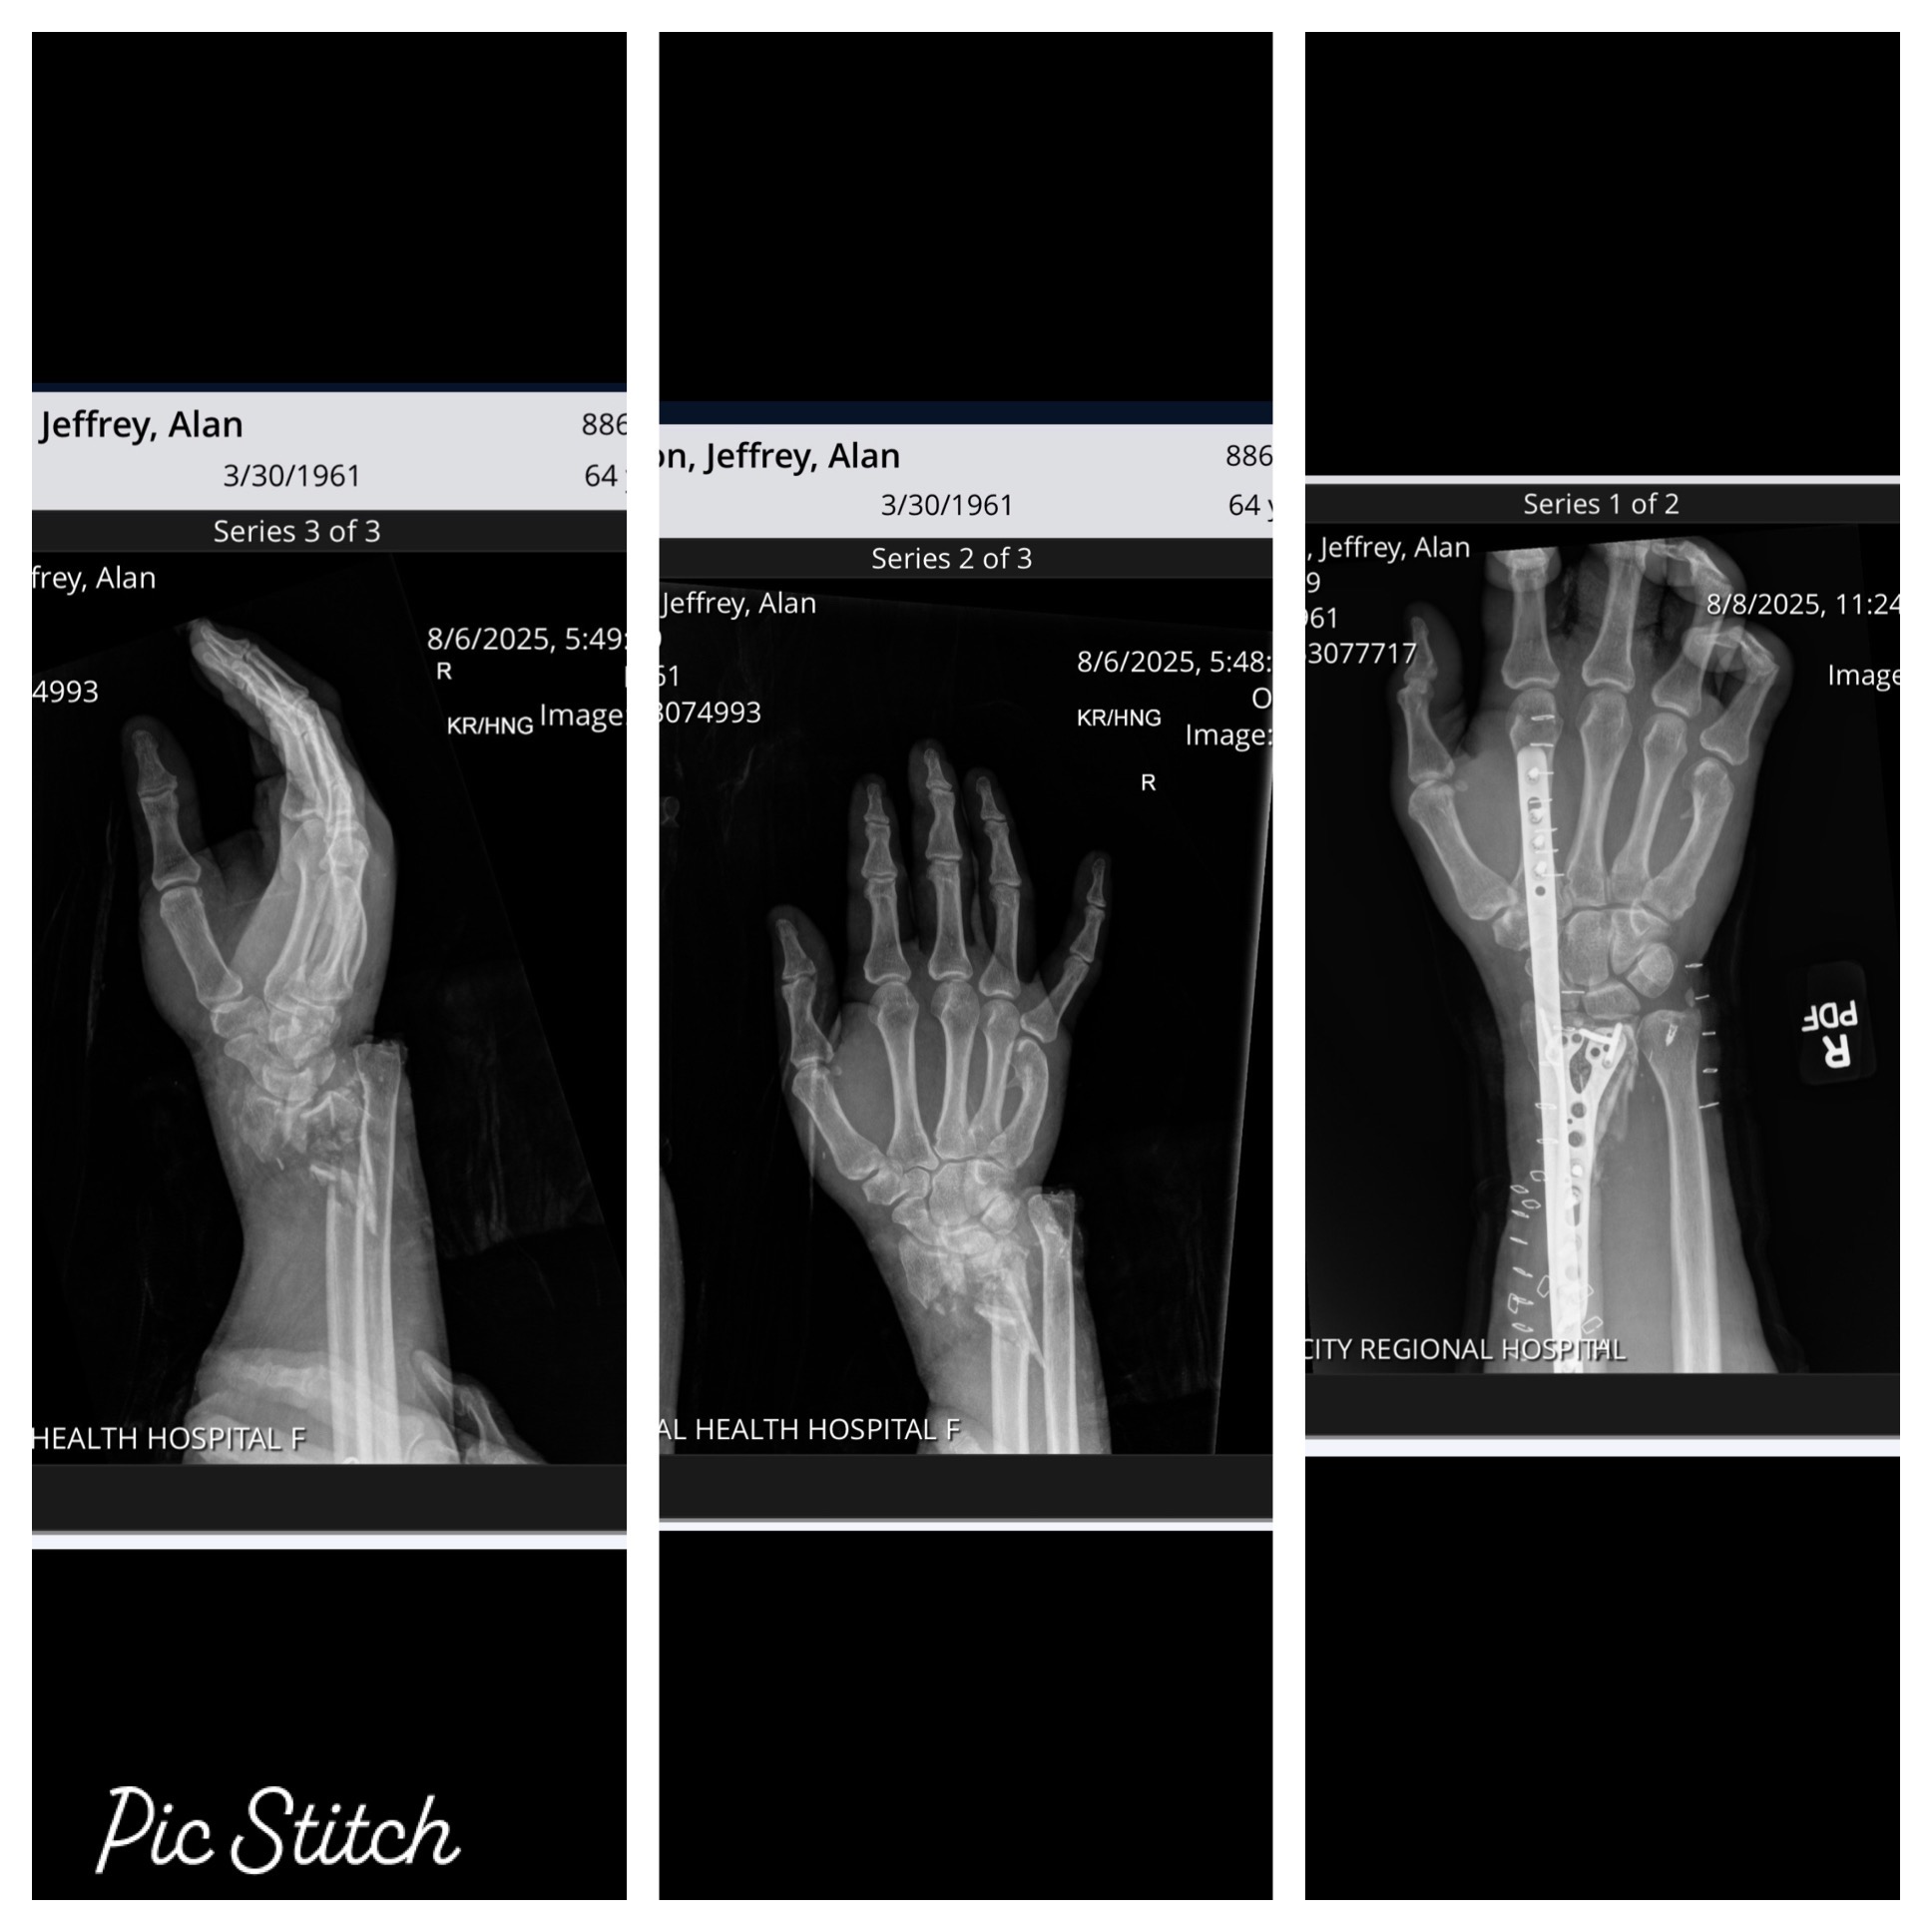

• Compound fractures of radius and ulna on right wrist requiring 13 cadaver bones, a plate, and screws in right arm. Three surgeries on wrist. The intensity blew apart his elbow which now has a plate and six screws.